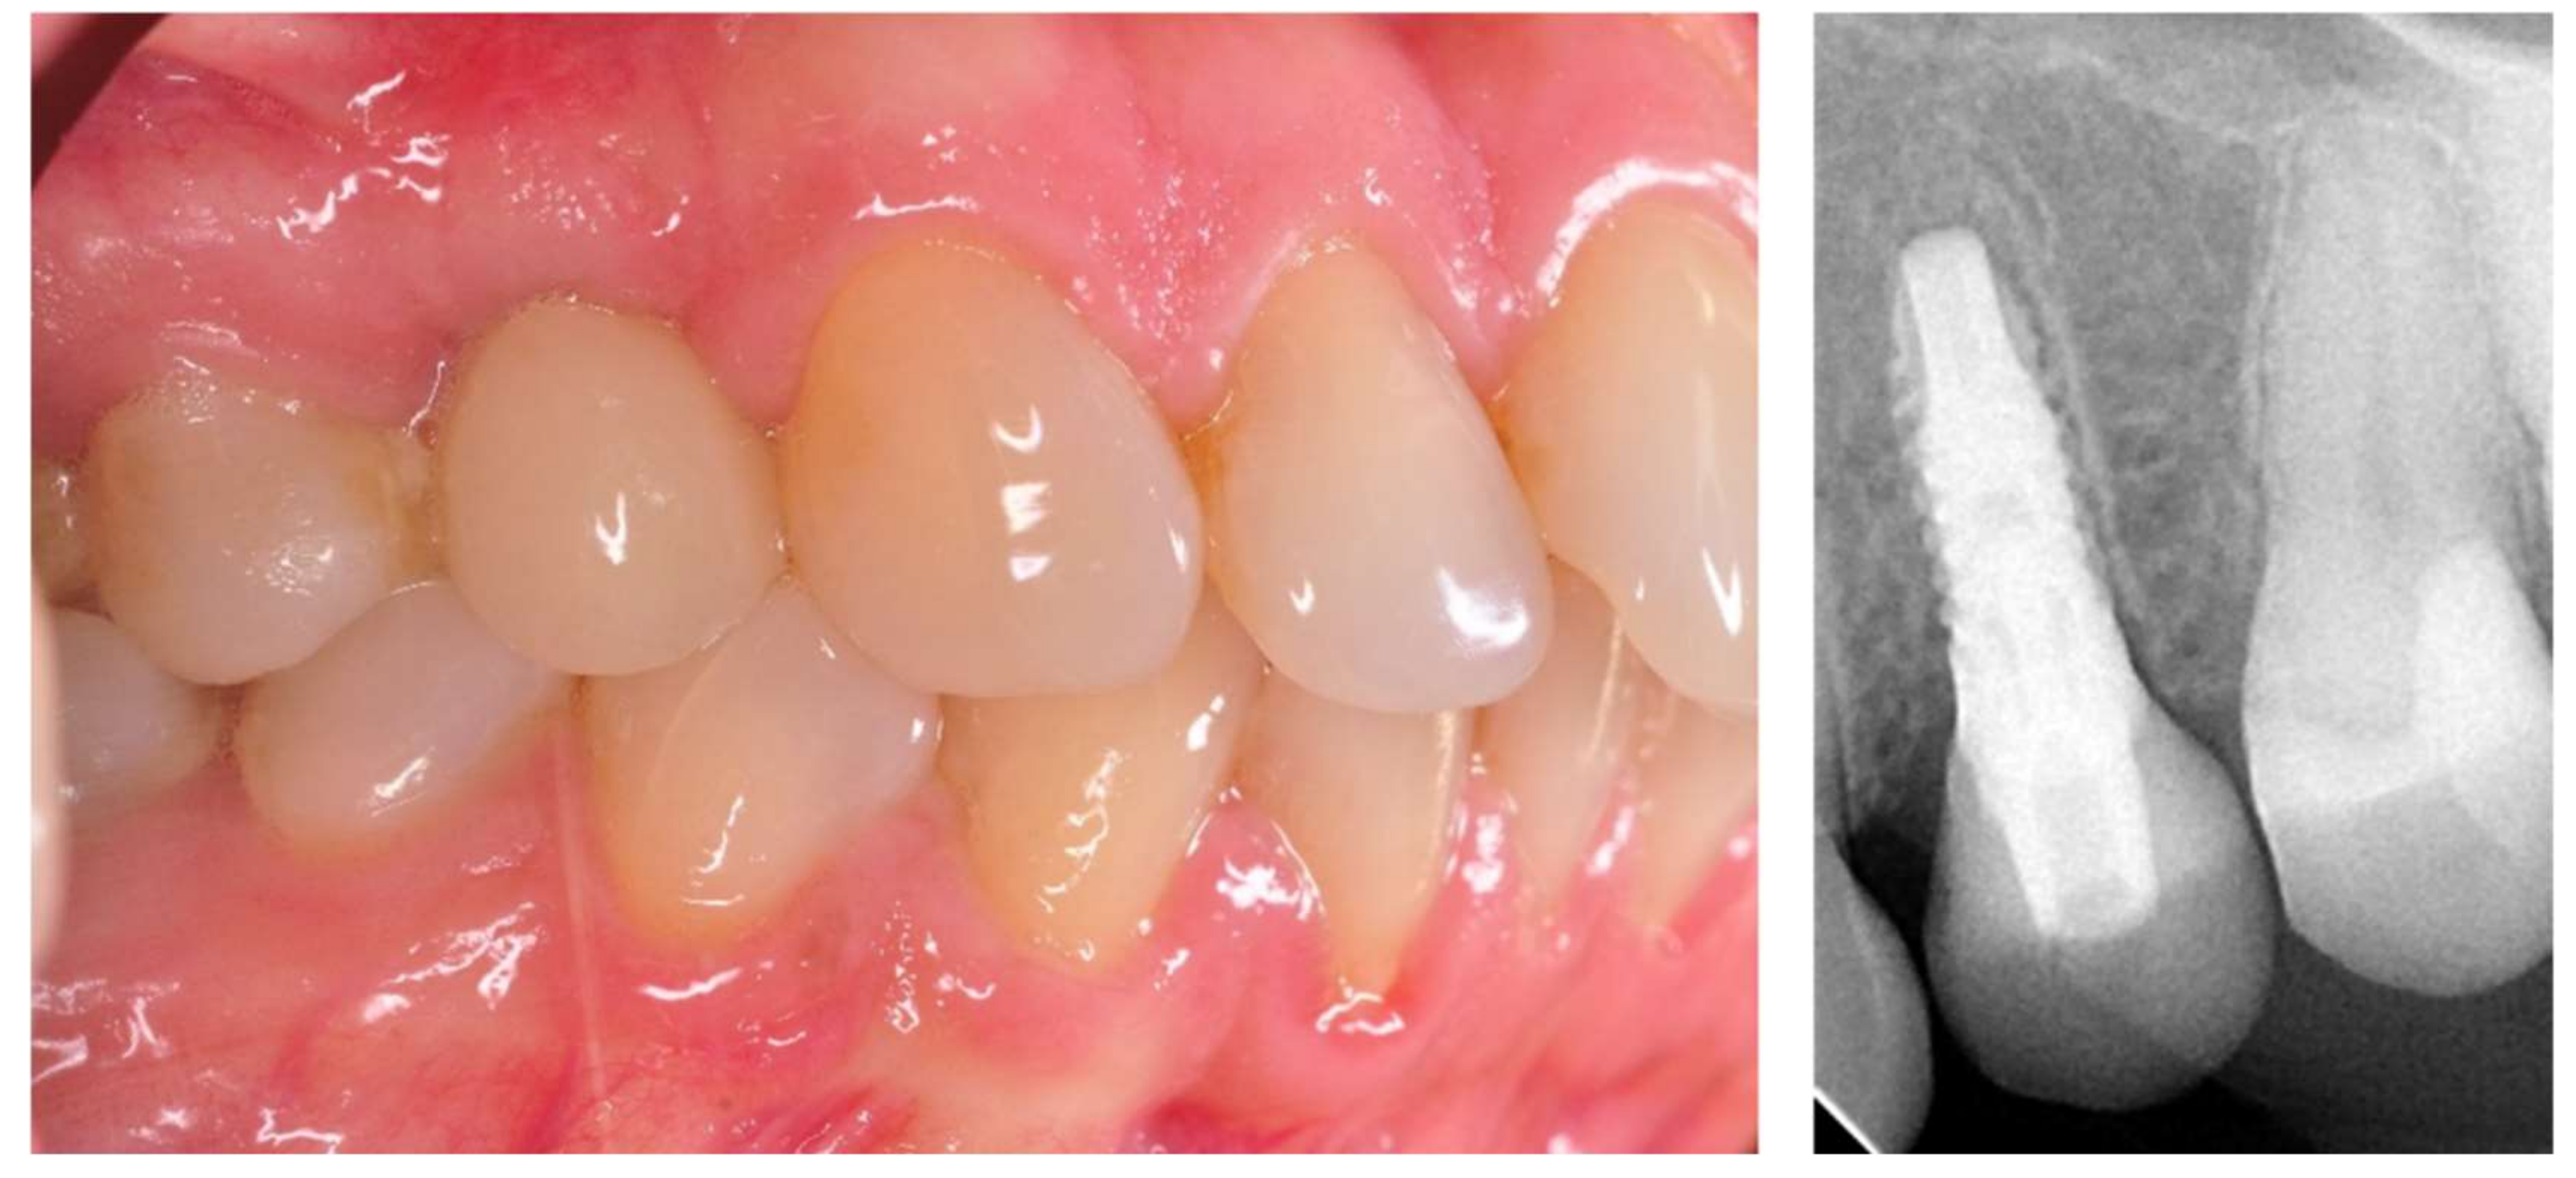

The prosthetic restoration stage started 4 weeks after the implant placement surgery and was prepared in the chairside laboratory by W.G. Patients with no signs of inflammation in the direct vicinity of the implant and with an ISQ (implant’s stability quotient) value of 65 or greater were allowed to participate in the prosthetic protocol. The measurements using the aforementioned device were performed three times in the mesiodistal, buccal and palatal, as well as periapical direction, and the smallest value was considered the cut-off point. Screw-retained implant crowns made of lithium disilicate glass-ceramics, IPS e max CAD LT (Ivoclar Vivadent AG, Schaan, Liechtenstein), were used as the prosthetic restoration materials. After the removal of the healing abutment, the implant bed was cleaned. The scans were taken with an intraoral scanner Sirona Cerec AC Bluecam (DentsplySirona, York, PA, USA) (Figure 2). Subsequently, the crown internal surface was etched and then fixed using Multilink Hybrid Abutment cement (Ivoclar Vivadent AG, Schaan, Liechtenstein) on the previously sandblasted titanium base (TiBase) for Sirona Cerec (DentsplySirona, York, PA, USA). The crown was then screwed onto the implant with a force of 25 Ncm. The occluding relations were controlled using articulating paper (Bausch®, Cologne, Germany) with a thickness of 200, 80, and 8 μm. The hole was filled in with Gradia composite (GC Corporation, Tokyo, Japan) and an RVG image was taken (Figure 3). The patients were instructed on proper hygiene around the dental implant.

Figure 2. Implant with scanbody prepared for intraoral scan.